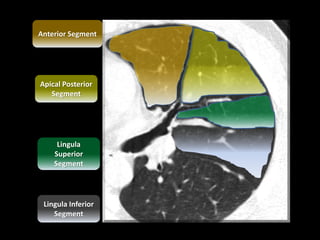

Ground-glass opacity at the level of the left upper lobar

bronchus

A. Apical Posterior

Segment

B. Anterior Segment

C. Lingula Superior

D. Lingula Inferior

Spur

LUL

APS

MF

Lingula Inferior

Lingula

Superior

Apical Posterior

Anterior Segment